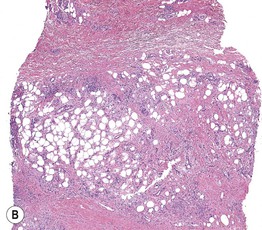

Fig. 1.12 Septal panniculitis. A Multiple red-brown nodules of erythema nodosum on the shins, admixed with healing bruise-like areas. B Predominantly septal granulomatous infiltrate with formation of characteristic Miescher's granulomas. A, Courtesy, Kenneth Greer, MD; B, Courtesy, Christine Ko, MD.